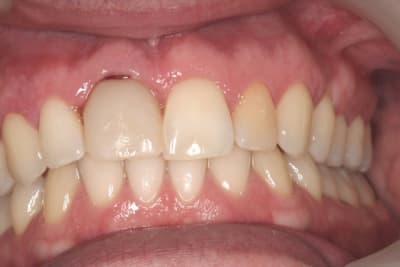

juste pour illustrer mon propos....

ici une MCI ou plutôt, devrais je dire une vis de cica anatomique immédiate.